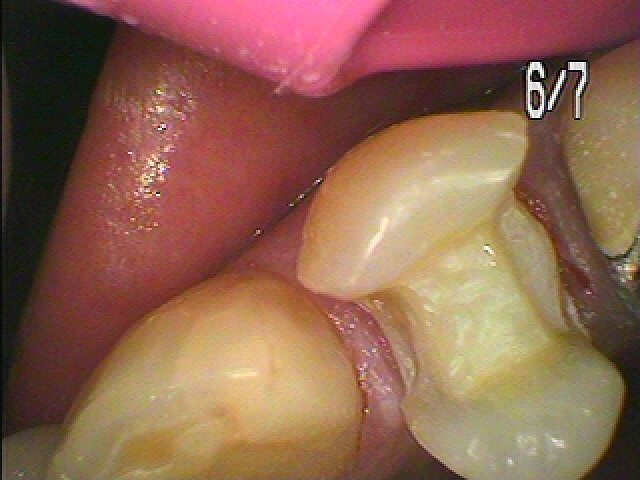

セラミックInのセットになります。右上小臼歯部になります。